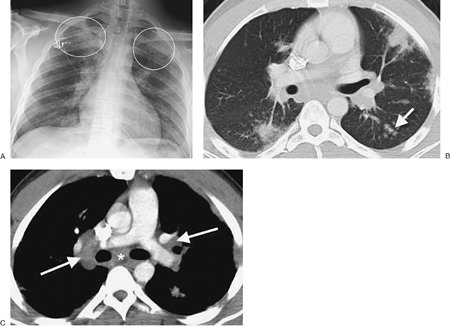

FIGURE 12-4. Alveolar sarcoidosis. A: PA chest radiograph of a 29-year-old man shows ill-defined opacities in the upper lungs (circles). B: CT image shows a peripheral distribution of airspace disease. Note nodular beading of a left lower lobe bronchovascular bundle (arrow), a characteristic feature of sarcoidosis. C: CT with mediastinal windowing shows bilateral hilar (arrows) and subcarinal (asterisk) lymphadenopathy. Most patients with alveolar sarcoidosis have accompanying lymphadenopathy.